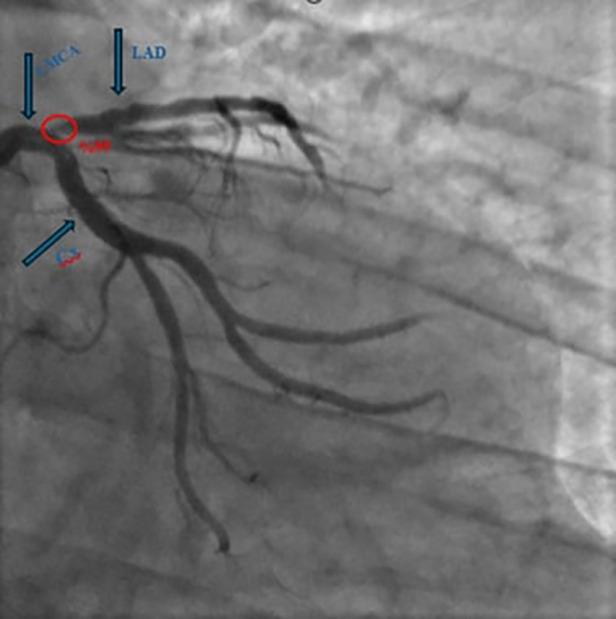

We present two male patients (aged 60 and 61) with ESLD and significant LAD stenosis who underwent simultaneous OPCAB and living donor liver transplantation (LDLT). The first case involved cryptogenic cirrhosis and recurrent variceal bleeding; the second had HBV/HDV-related cirrhosis and hepatocellular carcinoma. In both cases, OPCAB was performed using the left internal mammary artery (LIMA) graft on a beating heart. Subsequently, LDLT was carried out using standard piggy-back techniques. Portal pressure modulation via splenic artery ligation was performed in the first case due to elevated post-reperfusion portal flow. Anesthetic management emphasized hemodynamic monitoring and stability. Both patients were extubated on postoperative day one, discharged with triple immunosuppression, and followed for 6-12 months with preserved cardiac and graft function. A bile leak from the cystic duct anastomosis was encountered in one case.

我们报告了两名男性患者(年龄分别为60岁和61岁),患有ESLD且左前降支严重狭窄,他们同时接受了OPCAB和活体供肝肝移植(LDLT)。第一例患者为隐源性肝硬化并反复静脉曲张出血;第二例患有乙肝病毒/丁型肝炎病毒相关肝硬化和肝细胞癌。在这两例中,均在心脏跳动的情况下使用左乳内动脉(LIMA)移植物进行OPCAB。随后,采用标准背驮式技术进行LDLT。由于再灌注后门静脉血流升高,第一例患者通过脾动脉结扎进行门静脉压力调节。麻醉管理强调血流动力学监测和稳定性。两名患者均在术后第1天拔管,接受三联免疫抑制治疗出院,并随访6 - 12个月,心脏和移植物功能良好。其中一例出现胆囊管吻合口胆漏。